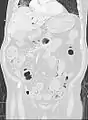

استرواح الأمعاء في التصوير المقطعي الإكليلي في نافذة الرئة. يمكن رؤيته بجوار انحباس الغاز في جدار الأمعاء والغاز في جدار المعدة وفي العديد من الأوعية، بما في ذلك الوريد البابي في الكبد.

تظهر الصورة الإكليلية MDCT المعاد تنسيقها الاسترواح المعوي المنتشر في الأمعاء الدقيقة الرباعية العلوية اليسرى. يكون الاسترواح المعوي أكثر تكيسًا وعقيديًا في الأمعاء الدقيقة في خط الوسط وعلى يمين خط الوسط. كان لدى هذا المريض عرض حميد نسبيًا بدون نفص تروية معوية وتمت معالجته بشكل تحفظي.